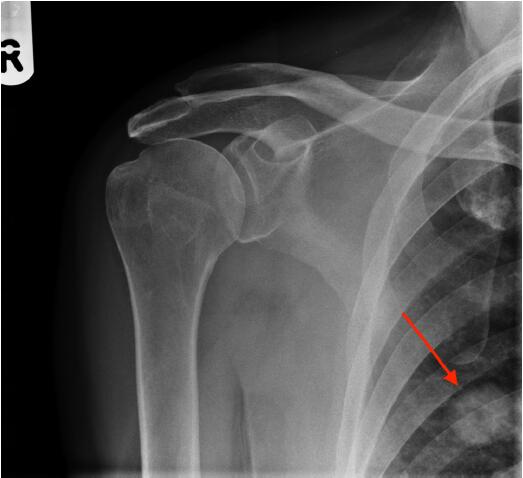

圖2肩X光片顯示一空洞性肺結(jié)節(jié),約2cm。很可能是原發(fā)性肺癌,需要轉(zhuǎn)診至肺癌多學(xué)科小組。

圖2右肩前位X光平片,紅色箭頭指示一空洞性肺結(jié)節(jié)

該例患者接受了胸部和腹部CT掃描,隨后取了活檢,證實為T2N0M0原發(fā)性肺腺癌。對給患者予以手術(shù)切除,2年隨訪時仍無病。